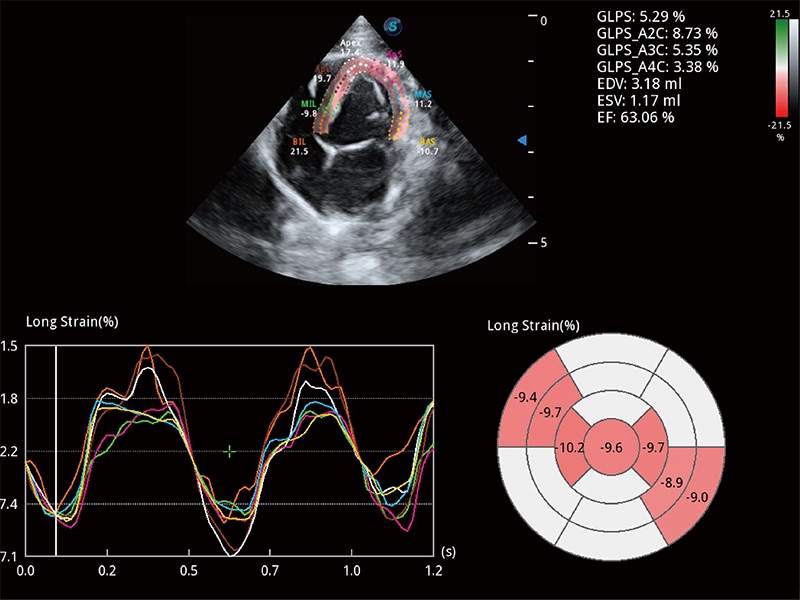

通过心肌识别技术与二维斑点追踪技术相结合,对心脏的超声图像进行量化分析。计算心肌17个节段的应变、应变率、速度、位移等,并通过牛眼图的形式进行呈现。

能够基于左心室壁追踪和辛普森法,自动计算射血分数,支持多个可移动点描迹,与手动测量相比,极大节省了动物医生的时间和精力。